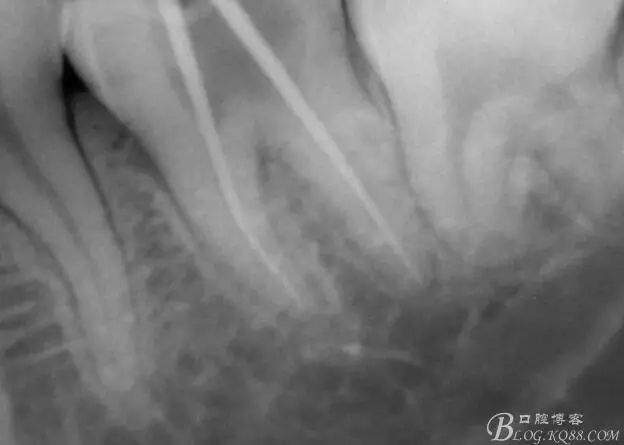

X線示牙膠尖到達(dá)工作長(zhǎng)度,故行AH-PLUSH糊劑配合卡瓦熱牙膠機(jī)運(yùn)用連續(xù)波充法根充,暫封拍根尖片。